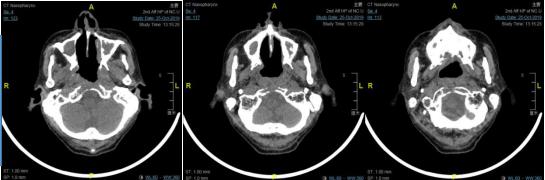

10月21日,南大二附院综合介入室陈平主任带领的介入团队于局麻下行血管介入下颈外动脉栓塞,完成介入手术后立即送至手术室,由盛洪广主任带领的麻醉团队成功完成全身麻醉,由耳鼻咽喉头颈外科鼻-鼻颅底团队在全身麻醉下行鼻内镜下鼻咽颅底肿瘤扩大切除术,术中顺利切除鼻咽部巨大肿瘤,并将侵犯蝶窦、斜坡、左侧破裂孔区肿瘤完整切除,术中出血不多,手术全程仅用时2小时。

手术后